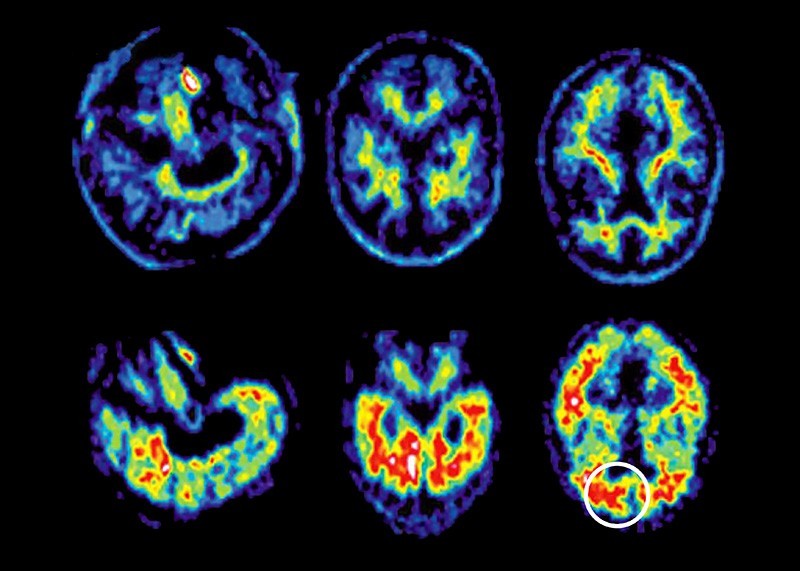

| Chụp cắt lớp não của một người bị bệnh Alzheimer. (Nguồn: SSPL) |